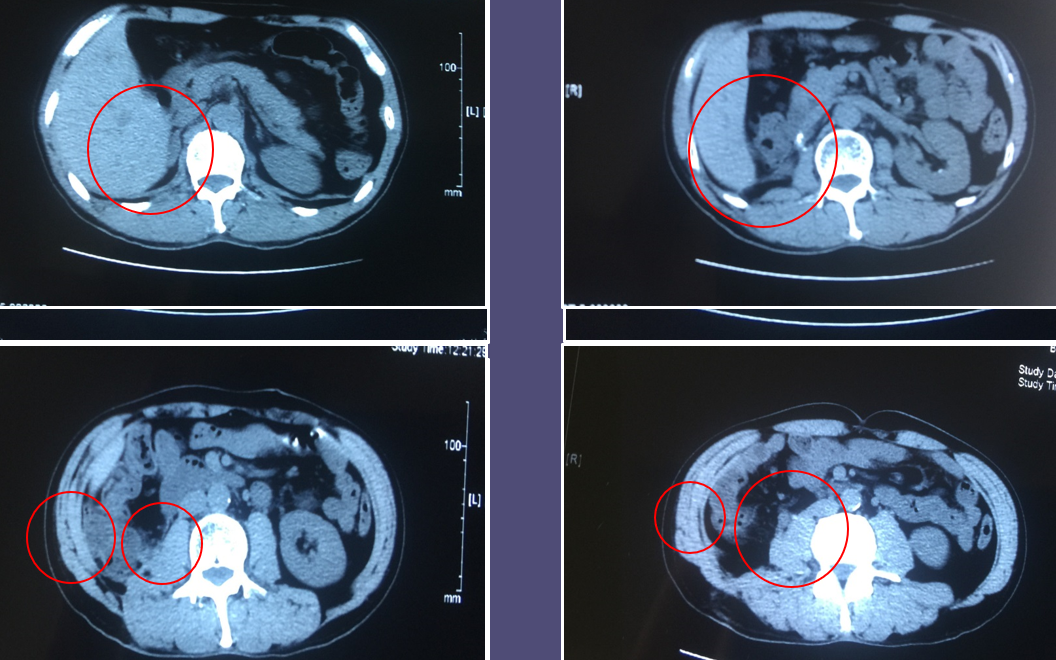

肺癌肾脏转移,也别太大意! - 好大夫在线

图片尺寸1096x573